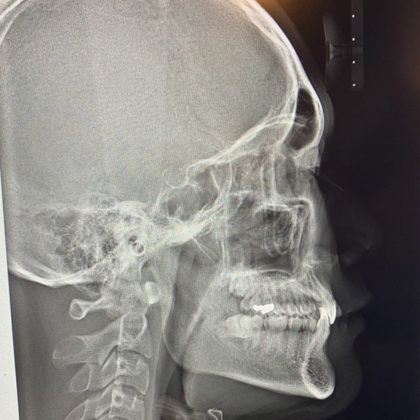

また年長さんは

初めて大人の歯が出てくる大事な時期です。

先日、幼稚園の年長さんを対象に

歯磨き教室を開催しました。